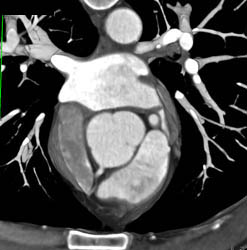

LAD and Circumflex Arise Directly Off Left Cusp